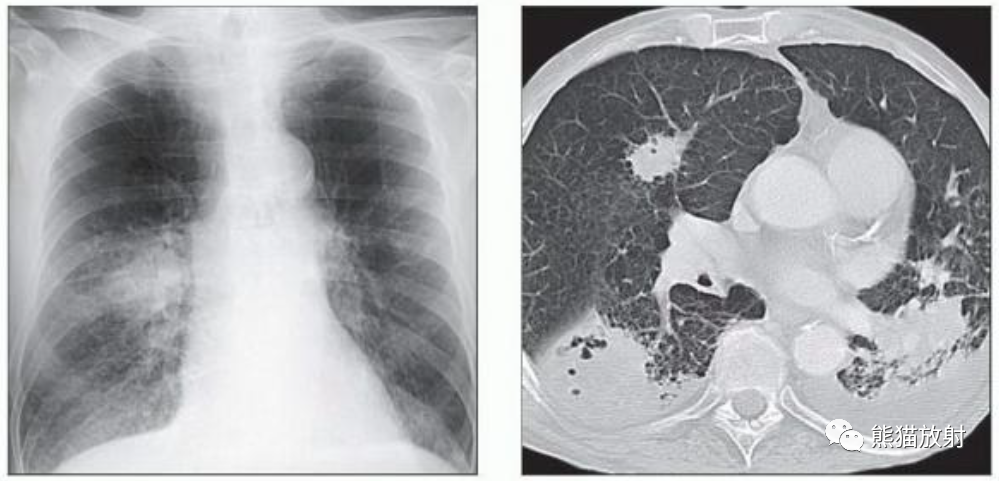

(左) 72岁男性,患有急性淋巴细胞白血病和中性粒细胞减少性发热。PA胸片显示双肺多发边界不清的结节。

(右) 同一患者,轴位CT显示多发部分实性肺结节,特征为中央软组织密度和外周磨玻璃影。虽然CT引导下活检证实了本例为侵袭性曲霉菌病,但通常可以根据临床表现和特征性的影像学表现进行治疗。

(左)26岁男性,患有急性髓细胞性白血病和中性粒细胞减少性发热。冠状NECT显示双肺多发结节,部分伴有磨玻璃影“晕征”。血清半乳甘露聚糖水平升高,推测诊断为侵袭性曲霉病,患者接受了2个月的伏立康唑治疗。

(右)同一患者治疗后,轴位NECT显示除右肺上叶小空洞结节外的所有病变均已消退。